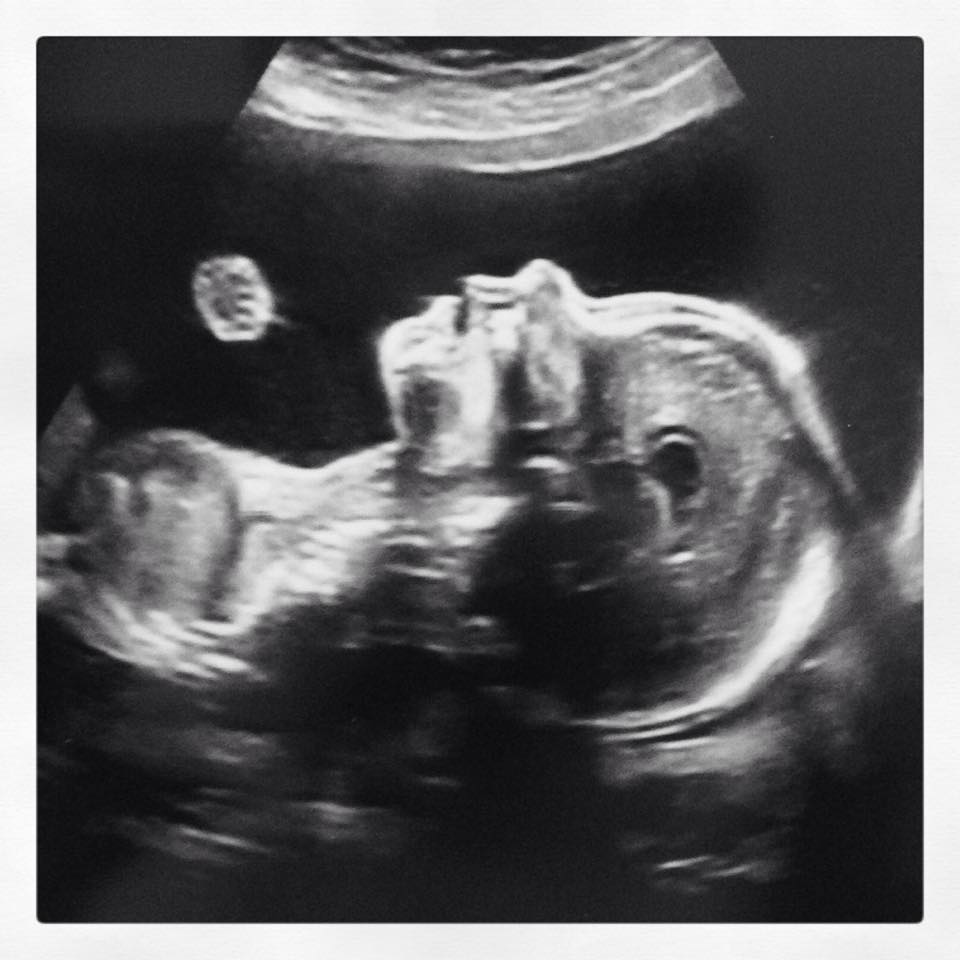

Darn i missed this one when it was originally posted Congrats on your little man! His bits were in the second photo :)